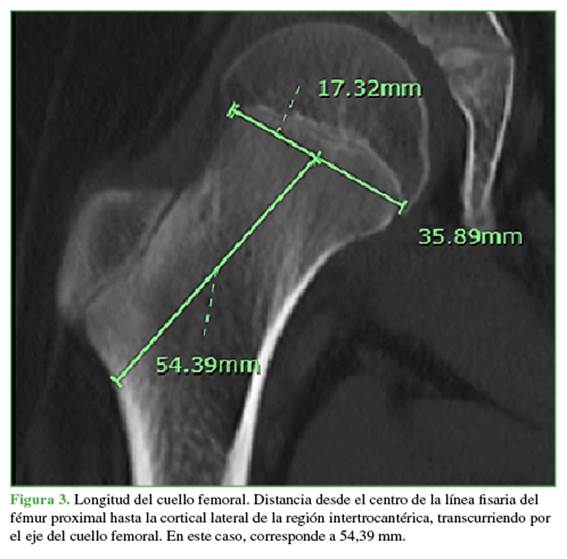

En los pacientes de 4 años o menos, se utilizó el método descrito por Amador y cols. para ubicar el centro de la cabeza femoral: se dibujó una secante que conecta los puntos más distales de las curvaturas medial y lateral metafisarias y una perpendicular en el centro de esta secante. El centro de la cabeza femoral es el punto sobre esta perpendicular que se ubica a la distancia desde la metáfisis descrita por Amador y cols. según la edad.9 El ángulo cervico-diafisario es el ángulo entre el eje del cuello femoral y el eje diafisario femoral en todos los casos (Figura 2).10

La longitud del cuello corresponde a la distancia desde el centro de la fisis del fémur proximal transcurriendo por el eje del cuello femoral hasta el eje de la diáfisis (Figura 3).

Se incluyó a 40 pacientes (promedio de edad, 9 años; rango de 6 meses a 18 años). El desplazamiento femoral muestra un crecimiento lineal en el tiempo con una tendencia a aumentar aproximadamente 1,96 mm al año hasta los 12.5 años, con un posterior aplanamiento de la curva y un aumento en el desplazamiento de 1,2 mm entre los 12.5 y 16 años (Figura 5). Respecto a la longitud del cuello femoral, la tendencia de crecimiento es constante, a una velocidad de 1,95 mm por año (Figura 6).